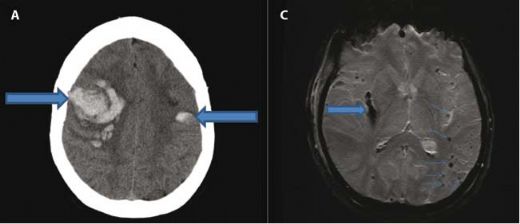

Subdural Kanama Belirtileri Ve TedavisiSubdural kanama, beynin dışındaki zarların arasında kan birikmesi durumunu ifade eder. Genellikle kafa travması sonrası ortaya çıkan bu durum, acil tıbbi müdahale gerektiren ciddi bir sağlık sorunudur. Bu makalede, subdural kanamanın belirtileri, tanı yöntemleri ve tedavi seçenekleri ele alınacaktır. Subdural Kanama Nedir? Subdural kanama, beyin zarı (dura mater) ile beyin arasındaki boşlukta kan birikmesiyle oluşur. Bu durum, genellikle kafa travması sonucu meydana gelir ancak bazı durumlarda, kan damarlarının zayıflaması veya çeşitli hastalıklar da subdural kanamaya yol açabilir. Subdural Kanamanın Belirtileri Subdural kanamanın belirtileri, kanamanın şiddetine ve süresine bağlı olarak değişiklik gösterebilir. Genel olarak, aşağıdaki belirtiler gözlemlenebilir:

Bu belirtiler, subdural kanamanın acil bir durum olduğunu gösterir ve derhal tıbbi yardım alınması gerektiğini ifade eder. Tanı Yöntemleri Subdural kanamanın tanısı genellikle aşağıdaki yöntemlerle konulur:

Tedavi Seçenekleri Subdural kanamanın tedavisi, kanamanın boyutuna, nedenine ve hastanın genel sağlık durumuna bağlı olarak değişir. Tedavi yöntemleri şunlardır:

Sonuç Subdural kanama, acil bir durum olup, belirtilerinin fark edilmesi ve hızlı bir şekilde tıbbi müdahale yapılması hayati önem taşır. Erken tanı ve tedavi, hastanın iyileşme sürecini olumlu yönde etkiler. Bu nedenle, kafa travması geçiren bireylerde belirtilerin gözlemlenmesi ve gerekli tetkiklerin yapılması önem arz etmektedir. Ek Bilgiler Bu makale, subdural kanamanın belirtileri ve tedavi yöntemleri hakkında genel bir bilgi sunmayı amaçlamaktadır. Herhangi bir sağlık sorunu durumunda mutlaka bir sağlık profesyoneline başvurulması gerektiği unutulmamalıdır. |